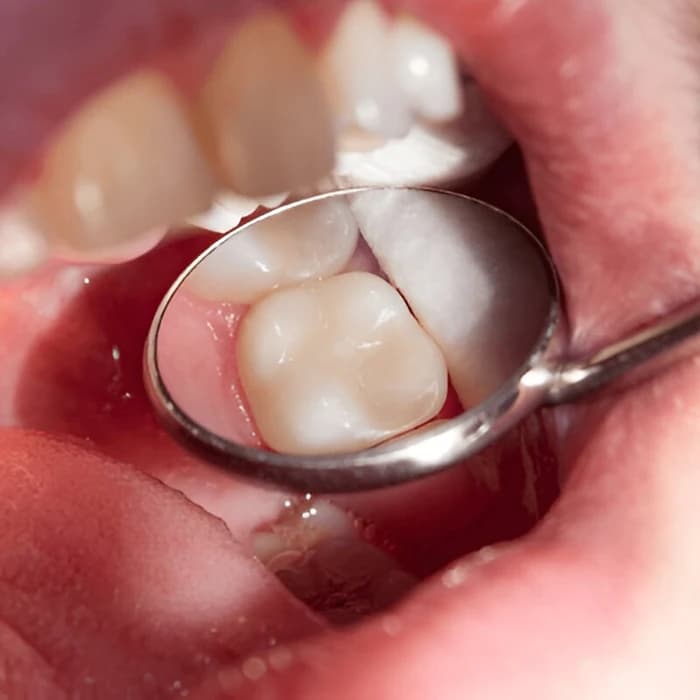

پر کردن دندان با مواد سفید و همرنگ دندان، مناسب دندانهای جلویی و عقبی

ترمیم پوسیدگی با کامپوزیت چیست و یعنی چی؟ به زبان ساده، این روش شامل استفاده از رزینهای کامپوزیتی همرنگ دندان است که برای پر کردن حفرههای ناشی از پوسیدگی یا آسیبهای جزئی به کار میروند. از دیدگاه علمی، این فرآیند بر اساس اصول دندانپزشکی ترمیمی طراحی شده و توسط انجمنهای معتبر مانند ADA (انجمن دندانپزشکی آمریکا) تأیید شده است. کامپوزیتها از ترکیب رزین و ذرات پرکننده مانند شیشه یا کوارتز ساخته میشوند که استحکام و زیبایی را بهطور همزمان ارائه میدهند. مطالعات در Journal of Dental Research نشان میدهند که این روش در بیش از ۸۵ درصد موارد، عملکردی مشابه دندان طبیعی دارد. اهمیت این درمان در حفظ ساختار دندان، جلوگیری از پیشرفت پوسیدگی و بهبود ظاهر لبخند نهفته است. برخلاف آمالگام، کامپوزیت به دلیل تطابق رنگ با دندان، گزینهای ایدهآل برای دندانهای جلویی است. این تعریف نه تنها جنبه درمانی، بلکه جنبه پیشگیرانهای دارد، زیرا از نیاز به درمانهای پیچیدهتر مانند عصبکشی جلوگیری میکند.

نحوه ترمیم پوسیدگی با کامپوزیت با مراحل دقیق و روشهای استاندارد انجام میشود تا بهترین نتیجه حاصل شود. ابتدا، دندانپزشک با بیحسی موضعی (مانند لیدوکائین) ناحیه را آماده میکند تا بیمار هیچ دردی احساس نکند. سپس، پوسیدگی با استفاده از دریل یا لیزر برداشته میشود و حفره تمیز و ضدعفونی میگردد. روش ترمیم پوسیدگی با کامپوزیت شامل اعمال اسید اچ برای افزایش چسبندگی و سپس قرار دادن رزین کامپوزیت بهصورت لایهلایه است. هر لایه با نور UV سخت میشود تا استحکام و یکپارچگی تضمین گردد. مراحل ترمیم پوسیدگی با کامپوزیت با پولیش نهایی تکمیل میشود تا سطح صاف و طبیعی به نظر برسد. این فرآیند معمولاً ۳۰ تا ۶۰ دقیقه طول میکشد و طبق مطالعات Clinical Oral Investigations، دقت آن در ترمیمهای سطحی به ۹۵ درصد میرسد. نحوه انجام این روش با استفاده از مواد نانوهیبریدی، دوام را تا ۷-۱۰ سال افزایش میدهد. در نهایت، دندانپزشک توصیههای مراقبتی مانند اجتناب از غذاهای سفت را ارائه میدهد تا ماندگاری درمان حفظ شود.